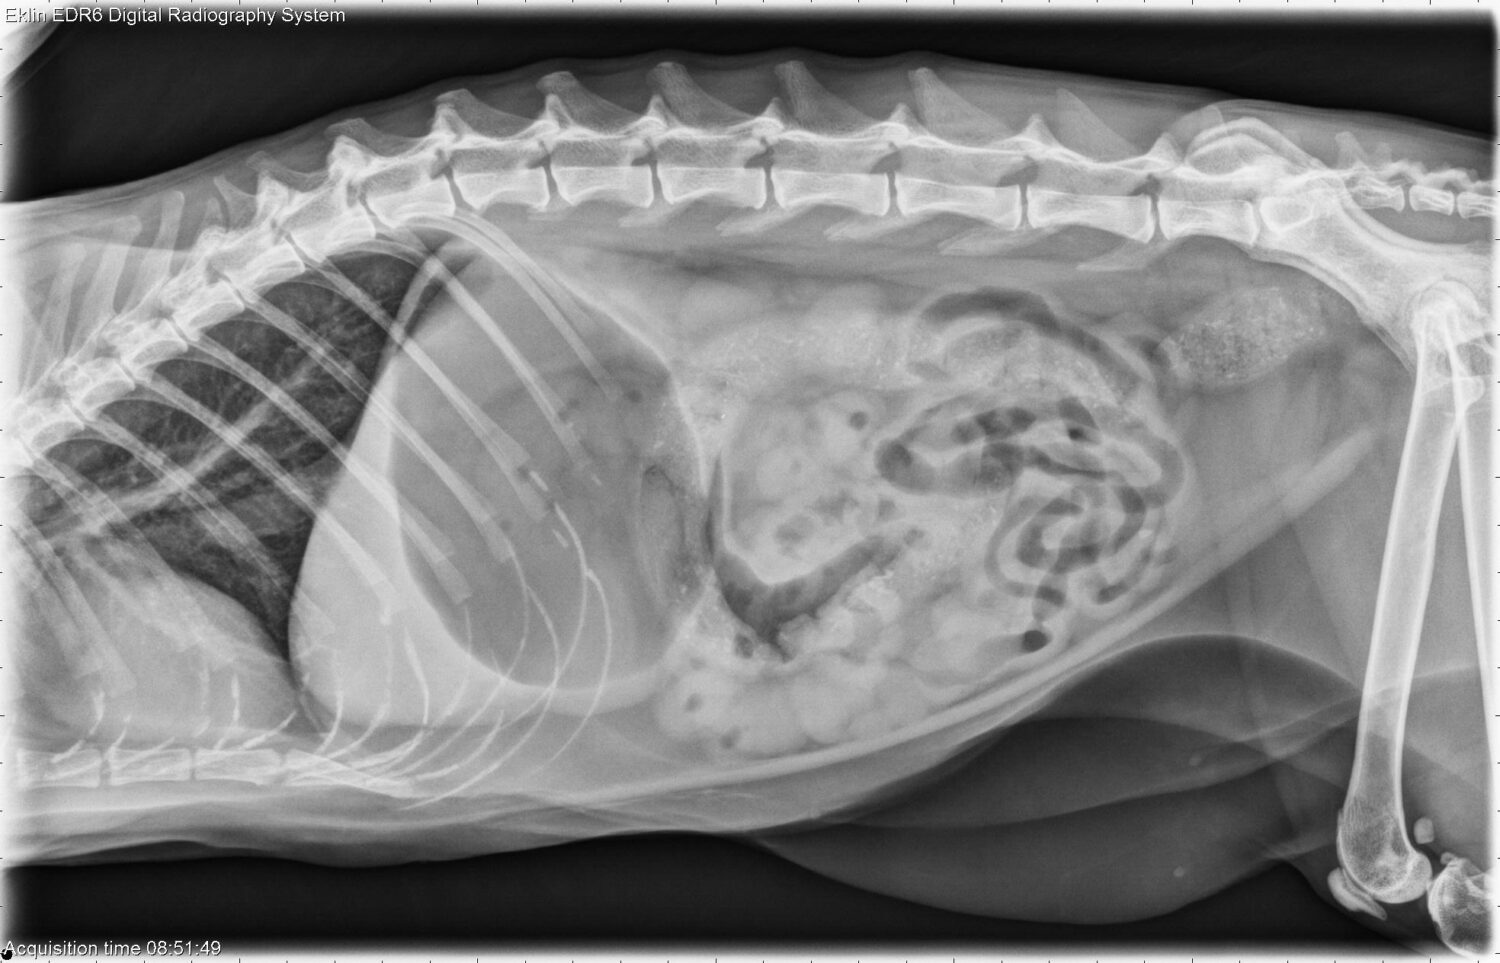

Van schaduw tot diagnose: leer kijken als een radioloog

In dit webinar uit de Klinische Cases-reeks neemt Dr. Emmelie Stock je mee door een reeks uiteenlopende radiografieën uit de dagelijkse praktijk. Stap voor stap leer je hoe je systematisch naar een beeld kijkt, subtiele afwijkingen herkent en radiografische bevindingen koppelt aan de klinische context.

Een ideale sessie om je radiologische blik te verscherpen, je klinisch redeneren te trainen en praktische inzichten op te doen die je meteen in de praktijk kan toepassen.